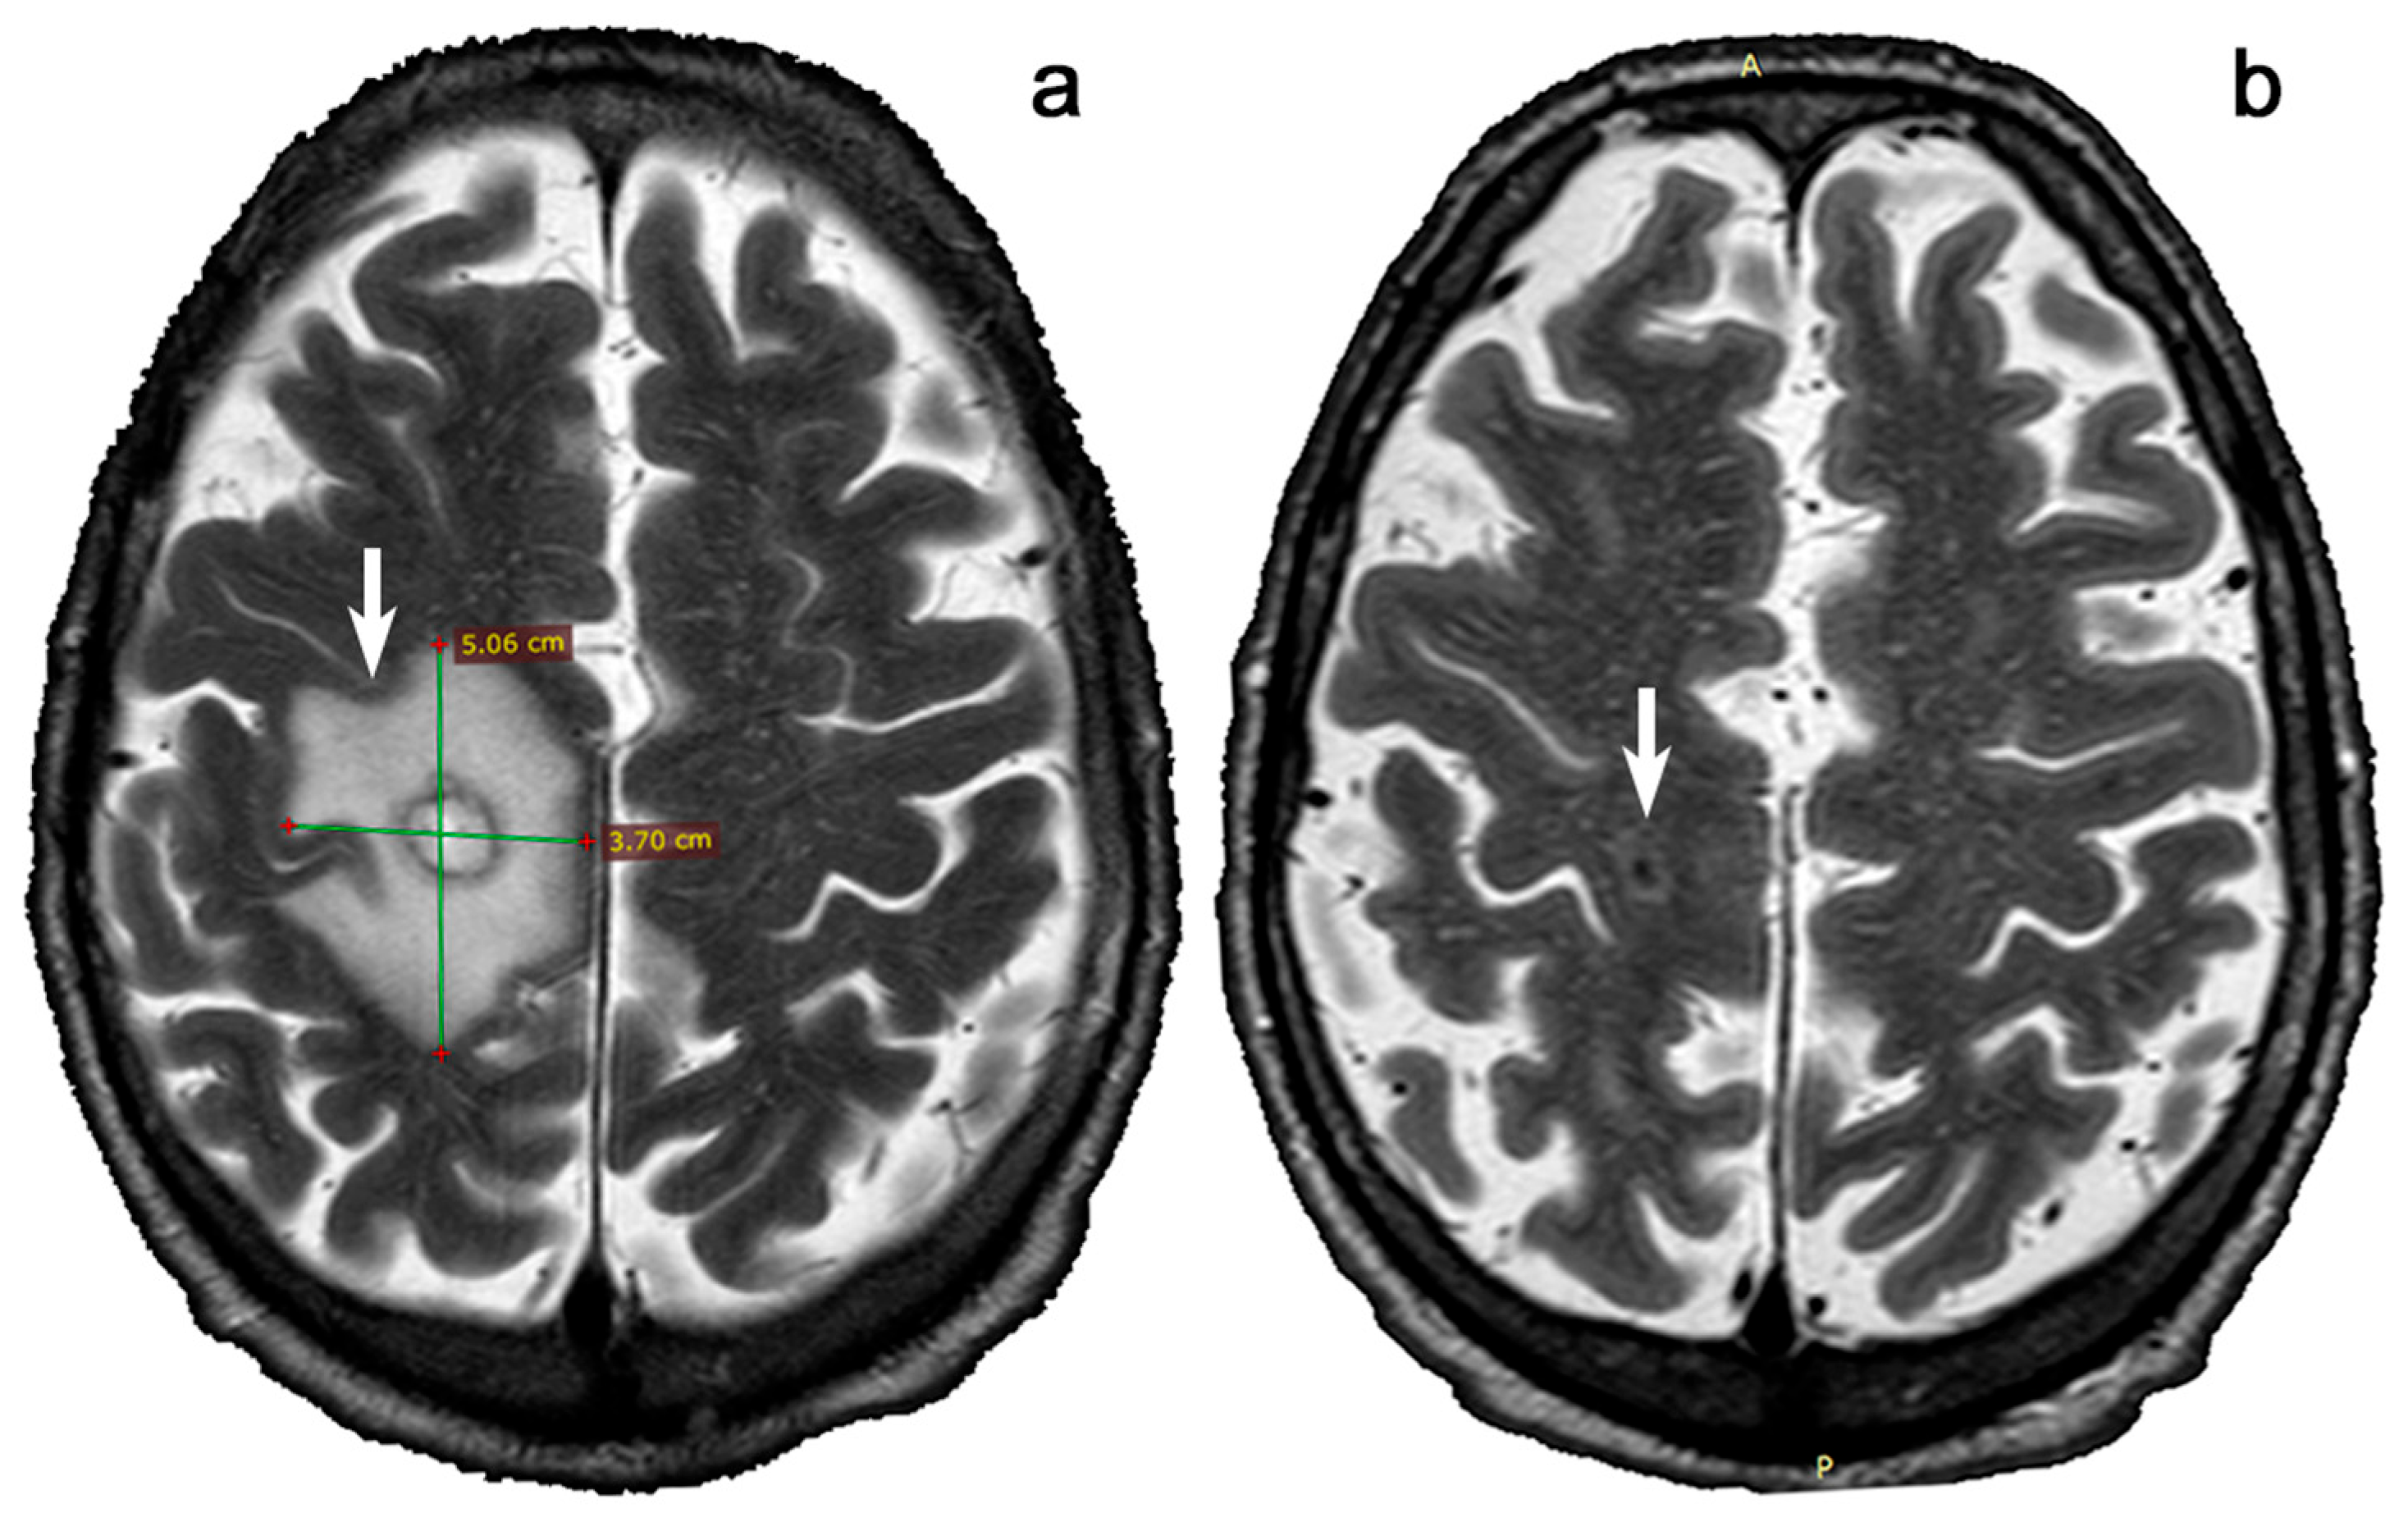

- Marra, C.M. Central nervous system infection with Toxoplasma gondii. Handb. Clin. Neurol. 2018, 152, 117–122. [Google Scholar] [CrossRef]